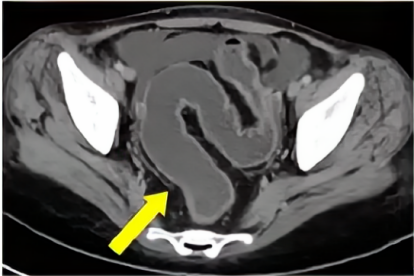

乙状结肠CT图片

乙状结肠为结肠的一部分,呈乙字形弯曲。上承降结肠,下接于直肠的一段结肠。有系膜固定,是憩室、肿瘤的好发部位。

乙状结肠位于左腹下部及小骨盆内,自左侧髂嵴处接降结肠,至第3骶椎上缘处续于直肠,呈“乙”状或“S”形弯曲。正常人除腹壁过厚者外,在左下腹可以触及,呈光滑、稍硬的圆桶状,粗细如蜡烛。小儿因年龄的不同而粗细不等,无压痛。